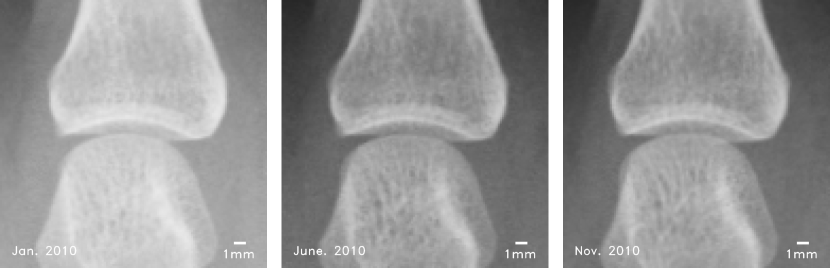

Refer to caption

Figure 1: JSN progression of a MCP joint for little finger over a period of 10 months. From left to right the images are: baseline, five-month, and ten-month images (spatial resolution: 0.175mm/pixel0.175𝑚𝑚𝑝𝑖𝑥𝑒𝑙0.175mm/pixel). Usually, JSN progression is less than one pixel per year, therefore, it is difficult for radiologist/rheumatologist to see. Then, operating with an algorithm with pixel level accuracy to quantify JSN over a period of one year can be ineffective. JSN measured for five and ten months X-rays relative to baseline using our method are 0.111pixel0.111𝑝𝑖𝑥𝑒𝑙-0.111pixel and 0.213pixel0.213𝑝𝑖𝑥𝑒𝑙0.213pixel respectively.